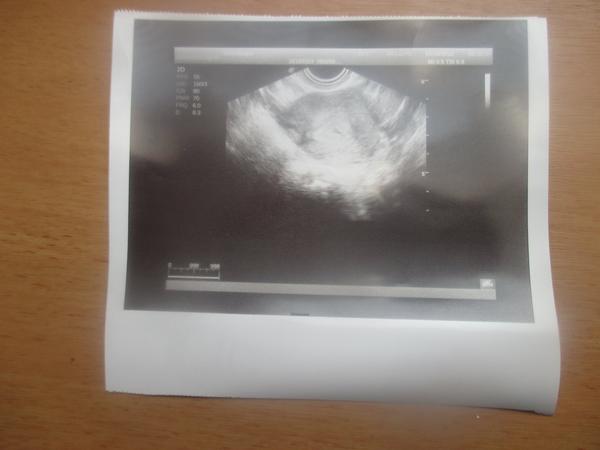

@lussinka88 ahojky když pracuješ v laborce,můžu se tě prosím na něco zeptat? 😀 já mám včerejší výsledky s HCG takto IU/I a mám 26,50 jak to teda je?dnes jsem byla na UTZ,protože mě docela pobolívá podbříšek tak jsem si nechala napsat nemocenskou... a už na UTZ jde vidět malinká tečka (těhotenství) tady je fotka... dr mi hned řekl,že jsem těhotná a ukazoval mi to i na UTZ.on se neplete,ale zase ta hodnota HCG mě plete 😀 když včera byla tak malá tak jak může už dnes něco být na UTZ? 🙂 moc děkuji za vysvětlení 🙂